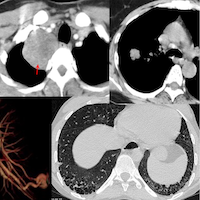

66-years old man presented with a mass in the spleen involving the tail of the pancreas.

Findings: Large splenic mass involving tail of pancreas

Complication: 75 cc bleeding perisplenic stable after the 1st hour

Diagnosis: Non-Hodgkin’s lymphoma, large B-cell type